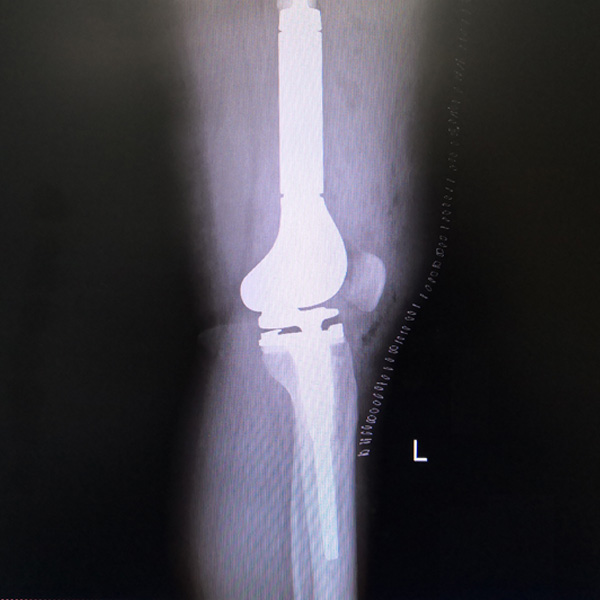

骨肉瘤手術(shù)

患者張某,女,14歲,診斷為“左股骨遠(yuǎn)端骨肉瘤”,當(dāng)?shù)蒯t(yī)院因?yàn)獒t(yī)療技術(shù)和能力的限制,只能考慮截肢手術(shù)。患者家屬通過平臺(tái)推薦,指定到哈......